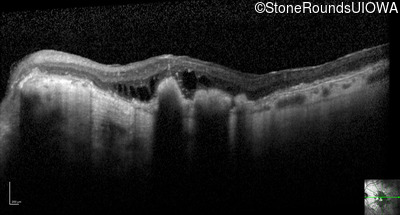

Optical Coherence Tomography - Right - Count Fingers 2'

Exemplar / OCT Stack